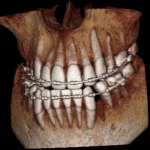

Why 3D?

Two Very Different Approaches to 3D Dentistry

How Big of a Field of View Do I Need for My Dental Cone Beam?